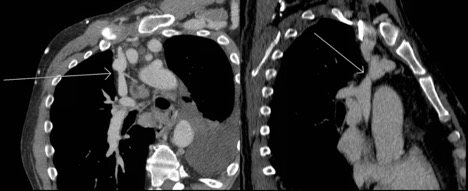

Figure 1. Oblique reformatted chest CT demonstrating nonocclusive stenosis of the distal portion of the SVC. Note the synechiae or "web" within the innominate vein.

Figure 2. Axial chest CT demonstrating occlusive stenosis of the central portion of the innominate vein and SVC confluence.

Given his chronic immunosuppression, he was admitted by internal medicine for initiation of intravenous (IV) antibiotics. Thoracic surgery, transplant infectious disease, and nephrology were consulted following admission. He underwent an echocardiogram, which did not demonstrate congestive heart failure. A computed tomography (CT) scan demonstrated right internal jugular occlusion, superior vena cava (SVC) stenosis, prominent thoracic venous collaterals, and cervical and mediastinal lymphadenopathy (Figures 1 and 2). His pleural fluid cytology and cultures were negative, but testing indicated the presence of chylomicrons and his triglyceride level was 1154 mg/dL, which was consistent with a chylothorax.